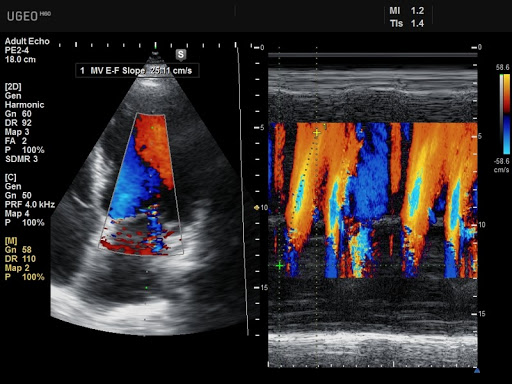

Цветные и тканевые М-режимы

Тканевое гармоническое эхо обеспечивает удвоение частоты приема УЗ волн. В результате получается более четкое изображение без артефактов, таких как боковые лучи. Изображение обрабатывается с помощью второй гармоники, отраженной от тканей.

В М-режиме происходит кодирование интенсивности принятых эхосигналов в виде яркости свечения точек дисплея.М-режим обеспечивает разверстку яркости свечения этих точек во времен и применяется в эхокардиографии.

Flow - цветной допплер - ЦДК. Учитывает приближающийся и удаляющийся кровоток, применяется для исследования кровотока в сосудах, в эхокардиографии. В сочетании с энергетическим допплером помогает в дифференциации кист и опухолей.

TDI - тканевой цветной допплер. Предназначен для визуализации миокарда. С его помощью изучают направления движения стенок левого и правого желудочков в систолу и диастолу тканевого допплера.

TDI PW - тканевой спектральный допплер. Использует цветовое двунаправленное или спектральное представление движения тканей сердца.

Дуплексные и триплексные режимы (B+Color+D)

Триплексный режим расширяет возможности дуплексного. Добавляет режимы цветного допплера, по которым можно наглядно судить о направлении кровотока и его скорости, Также позволяет более точно оценить проходимость сосудов и степень стеноза.